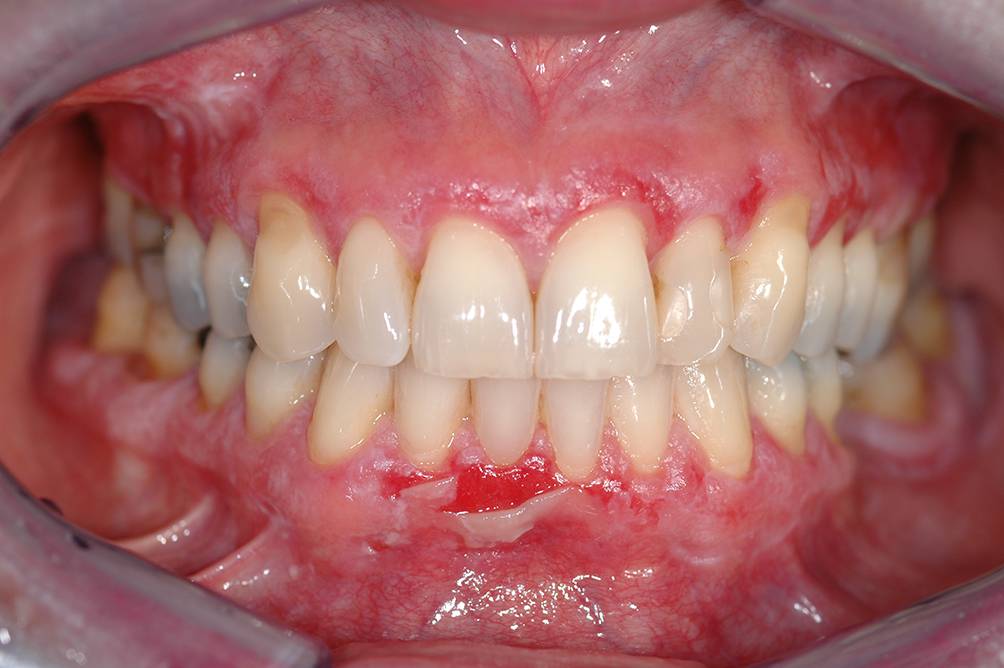

Abb. 9

Der bullöse Typ eines oralen Lichen planus (OLP) ist eher selten klinisch anzutreffen, da die Bläschen rasch platzen und in mit Fibrin belegte Ulzerationen übergehen. Hier imponiert eine geplatzte Blase bei einer 61-jährigen Patientin mit bekanntem OLP an der keratinisierten Gingiva im Frontzahnbereich des Unterkiefers bukkal. Diese OLP-Form ist i. d. R. symptomatisch und auch differenzialdiagnostisch relevant (Ausschluss von Mukodermatosen, v. a. des Schleimhautpemphigoids)

Bild vergrößern